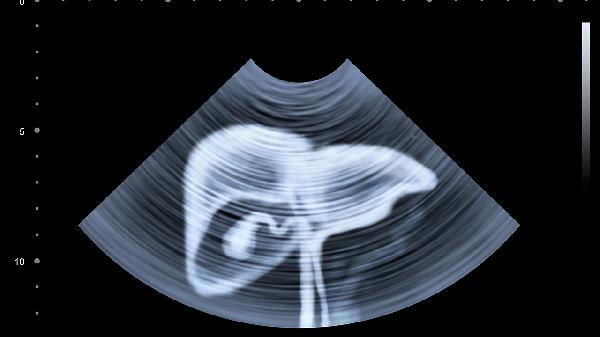

肝脏密度弥漫性减低是什么意思

肝脏密度弥漫性减低是影像学检查中的一种描述,指肝脏整体密度低于正常水平,可能与脂肪肝、慢性肝炎、肝硬化、肝淤血、代谢性疾病等因素有关。